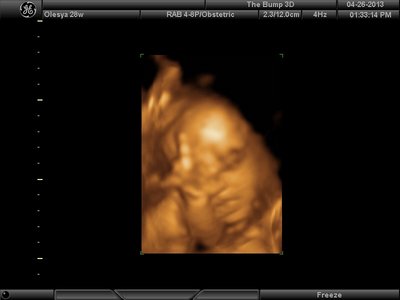

А я вчера на 3Д УЗИ ходила. Моя звезда закрывалась в еми 4мя конечностями. Просто пополам сложилась и спала себе сладко. УЗИстка провела со мной час, кое-как расшевелили маленькую, но ручка была постоянно на мордашке и засыпала она почти сразу снова. Я и на мяче прыгала и живот трясла. В конце более-менее фото вышли, но качество меня не порадовало. Возможно фри оф чардж еще раз переделают. Со средней фотки были отличного качества, а эти сплошное разочарование. Вот тут что-то более-менее еще. Главное пальчик оттопырила так смешно, мол минуточку. Вообще немного жутковатые фотки..хаха

| Вложения: |

image.jpg [ 47.86 КБ | Просмотров: 1456 ]

Еще одна, качество ужасное..

image.jpg [ 60.32 КБ | Просмотров: 1453 ]